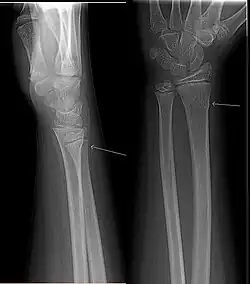

Une fracture en bois vert est un type de fracture osseuse fréquent chez l'enfant. C'est une fracture située au niveau de la diaphyse de l'os due à une contrainte en hyperflexion. Il s'agit d'une fracture d'une seule corticale avec une rupture du périoste en regard, tandis que le périoste et la corticale du côté de la concavité sont intacts[1]. C'est une fracture stable grâce à la persistance de la charnière périostée, avec néanmoins un risque de déplacement secondaire. C'est une fracture de bon pronostic.